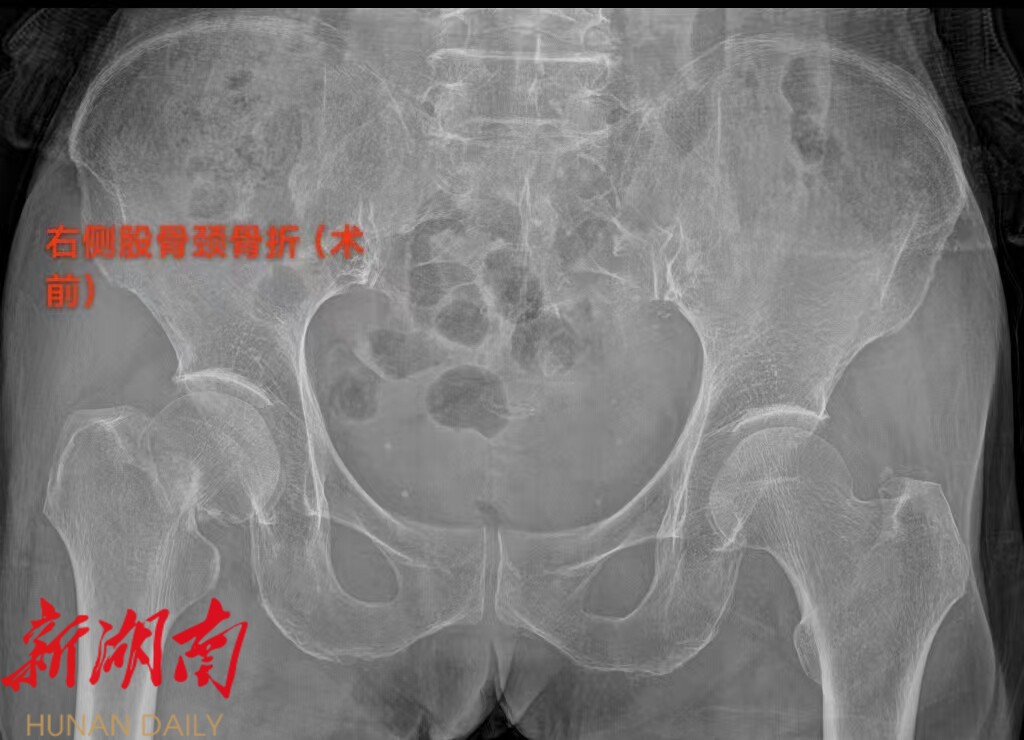

81 岁患者的朱奶奶,因摔伤致右髋部疼痛 2 天入院,确诊为右侧股骨颈骨折。永兴县人民医院骨二科团队在充分评估朱奶奶的病情后,决定采用 “保留梨状肌人工股骨头置换术”,术后第一天,朱奶奶便在医护人员的保护下顺利下地站立并行走,疼痛感明显减轻,关节活动功能恢复良好。